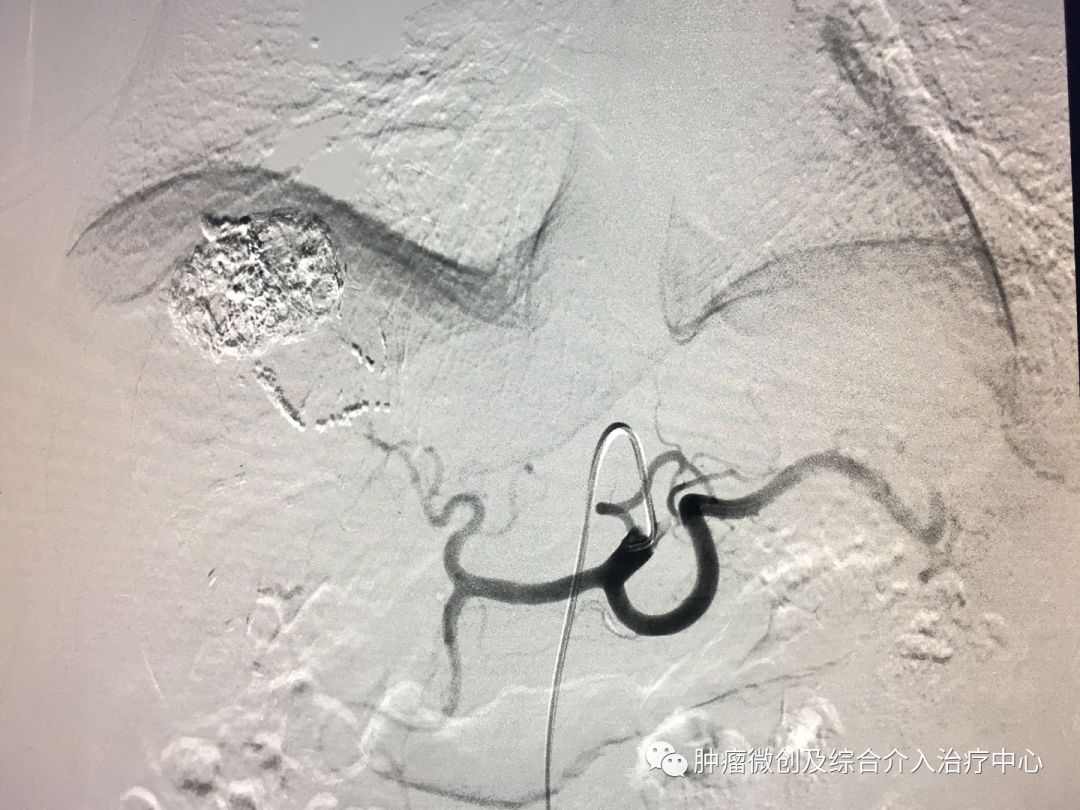

(术前DSA造影提示支气管动脉增粗、增多、絮乱,床表现为咯血,经久不愈)

(介入栓塞术后造影提示支气管动脉走向规则,清晰,术后咯血症状停止)